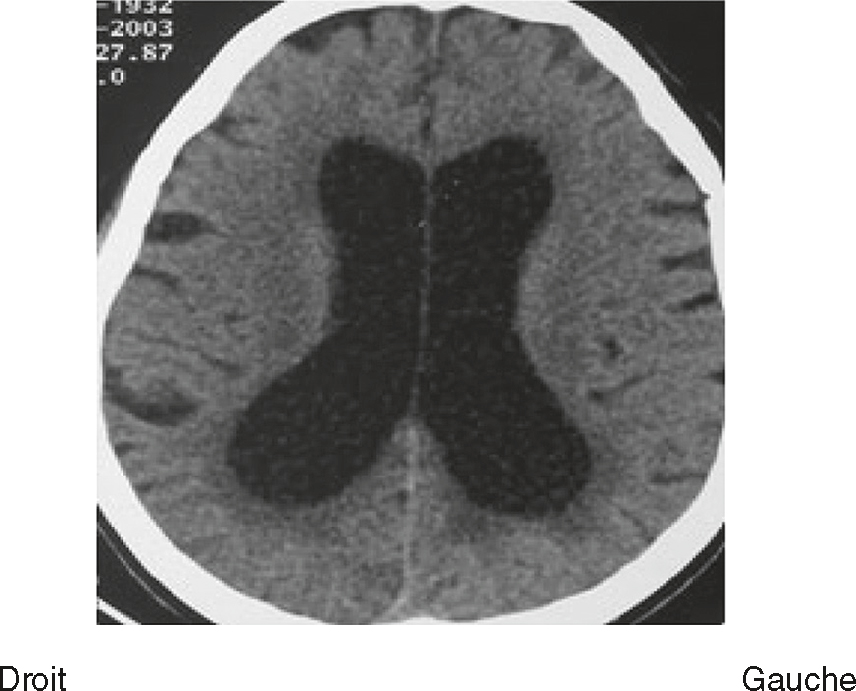

Une IRM encéphalique est réalisée (fig. 31.7). Sur cette planche, quels sont les éléments évocateurs du diagnostic de sclérose en plaques (SEP) ?

L'image montre trois coupes transversales d'un cerveau humain prises par imagerie par résonance magnétique (IRM). Chaque coupe est étiquetée avec des informations spécifiques : "FH 14 head", "FH 20 head" et "FH 26 head". Ces étiquettes indiquent probablement différentes sections ou niveaux de la tête. Les images montrent des zones de signal hyperintense, qui apparaissent comme des taches blanches sur les images. Ces zones peuvent indiquer des anomalies telles que des lésions, des plaques ou d'autres types de pathologies cérébrales. Les coupes transversales permettent de visualiser différentes parties du cerveau, y compris les ventricules cérébraux et la matière blanche environnante. Les images sont intéressantes car elles permettent de détecter et de surveiller des conditions neurologiques, d'évaluer l'étendue des dommages et de planifier des traitements appropriés. Les variations dans les images peuvent fournir des informations cruciales sur la progression de la maladie ou l'efficacité des interventions thérapeutiques.

- A 585présence d’hypersignaux de la substance blanche

- B localisation surtout périventriculaire des hypersignaux

- C aspect arrondi des hypersignaux

- D présence de trous noirs

- E atrophie cérébrale marquée